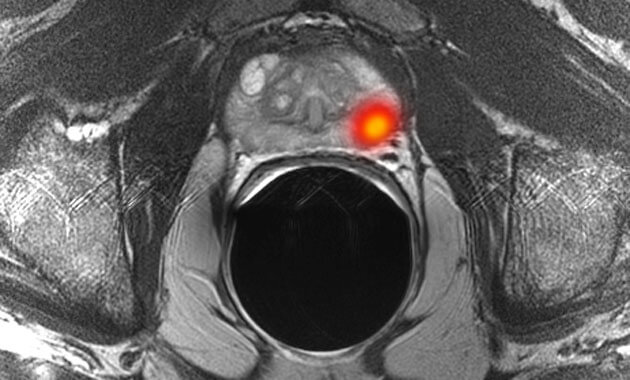

- Prostate tumors/cancer